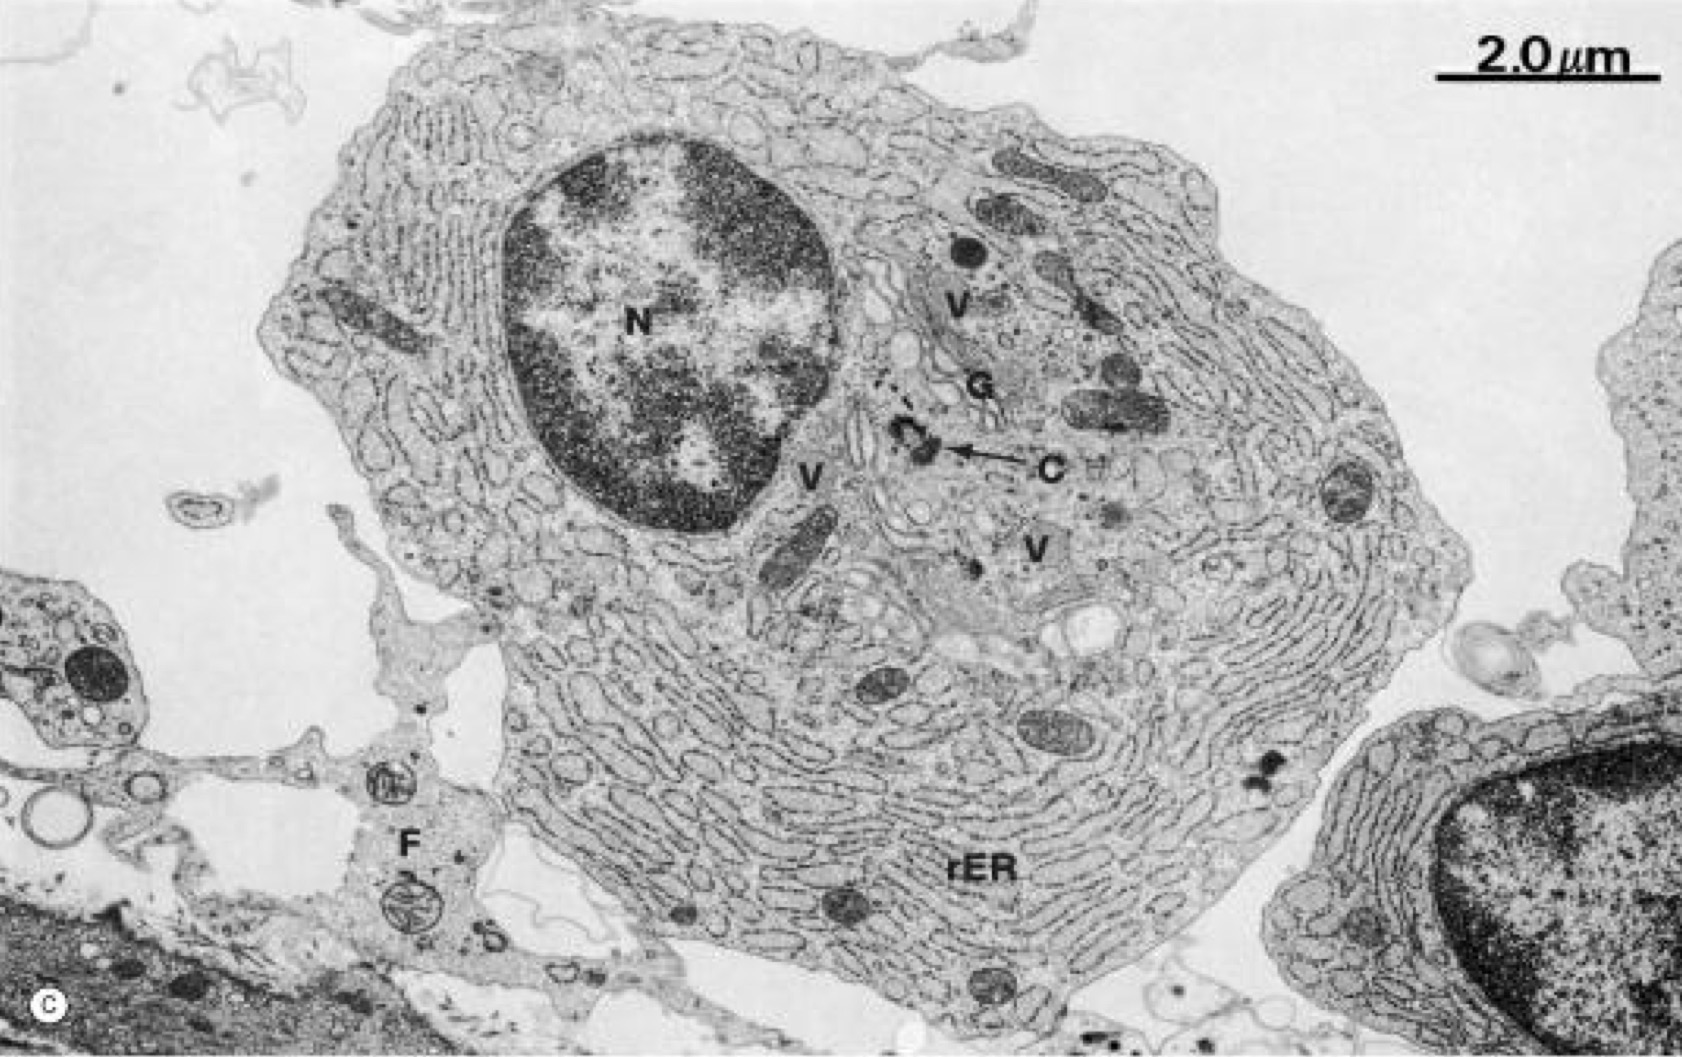

A- identify

B- Histological features

C- Function

D- Sites

A- white adipose CT

B- Cell: oval, unilocular adipocyte

Nucleus: flat and peripheral

Cytoplasm:Thin rim , one large fat droplet ,(signet ring appearance)

Separated by loose Ct

Less blood capillaries

Type of stain : stains orange in Sudan III

EM: few mitochondria and SER around nucleus

C- Storage fat, support organs. Heat insulator

D- perinephric fat , subcutaneous tissue

A- Brown adipocyte CT

B-Cell: rounded multilocular adipocyte

nucleus: central, rounded.

Cytoplasm: profuse , multiple fat small droplets

more blood capillaries

EM : numerous mitochondria surrounding the fat droplets

C- Heat generation

D- mediastinum , between 2 scapula

B- features / give a comment

A- White Adipose connective tissue

B-Cell: Unilocular Adipocyte that are rounded or oval cells

Cytoplasm:Thin rim , one large fat droplet ,(signet ring appearance) , less blood capillary surround it , separated by Loose CT

EM: few Mitochondria , SER around the nucleus

Site : Subcutaneous tissue , Perinephric fat

Function:Storage fat , support organs , Heat insulator